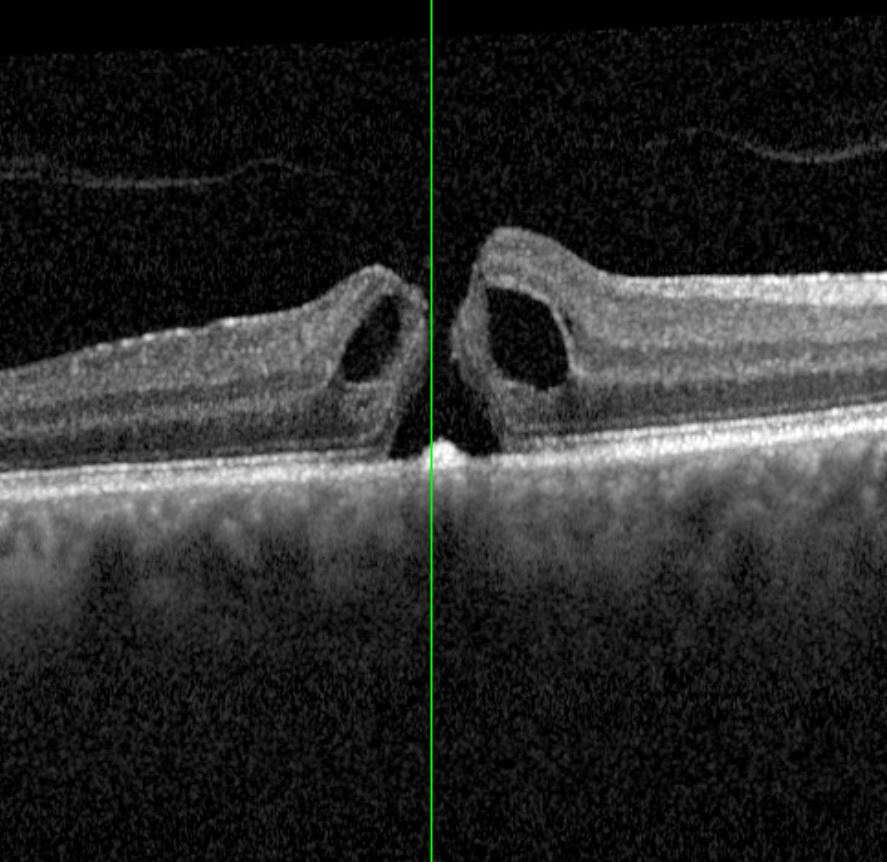

Es gibt viele unterschiedliche Netzhauterkrankungen, welche sich mit diversen Symptomen äußern. Hierzu zählen zB die epiretinale Gliose, Thrombosen, diabetische Veränderungen, Maculaforamen oder Netzhautablösungen.

Durch modernste Techniken haben wir die Möglichkeit Ihre Netzhaut zu untersuchen. Sollte bei Ihnen ein chirurgischer Eingriff (pars plana Vitrektomie) oder eine Therapie mit intravitrealer Medikamenteneingabe (IVOM) nötig sein, so können wir dies in unserer Klinik durchführen.